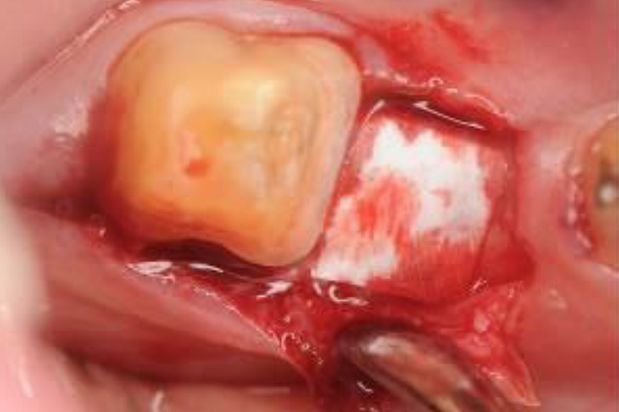

02/06 - Intra-operative view. Cleaned intrabony defect.Intrabony defect treated using Straumann® Emdogain®, cerabone® and Jason® membrane - Dr. D. B. Hangyási

03/06 - Straumann® Emdogain® applied to the defect area.Intrabony defect treated using Straumann® Emdogain®, cerabone® and Jason® membrane - Dr. D. B. Hangyási